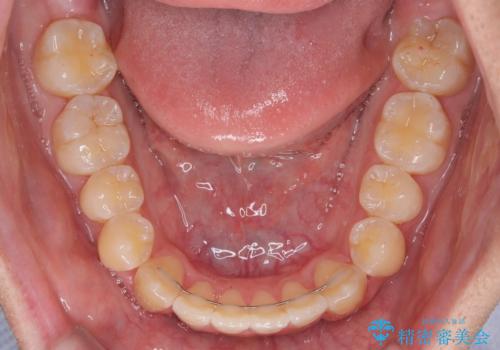

- インビザライン

- 1年11ヶ月